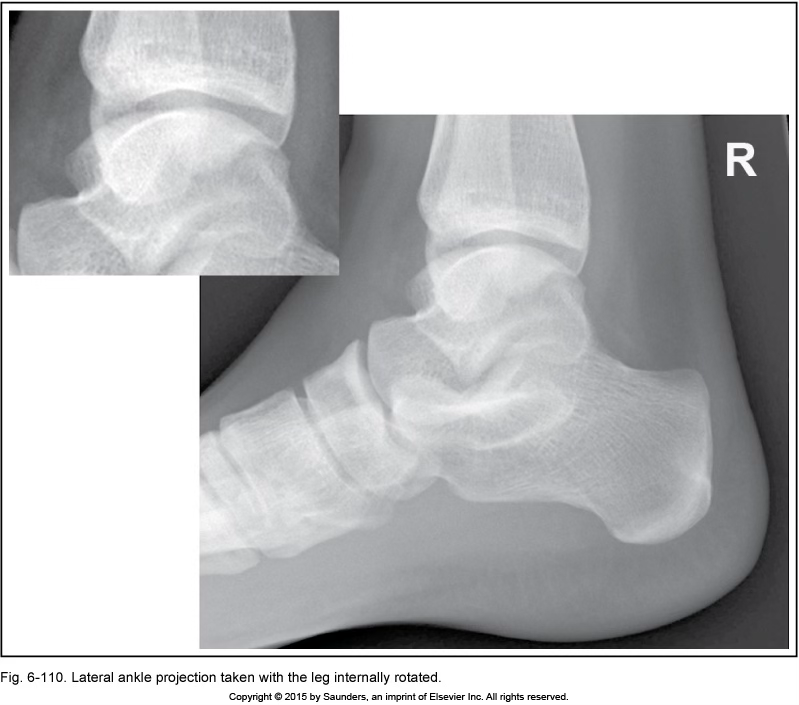

lateral ankle

leg internally rotated

sinus tarsi closed

fibula not in center